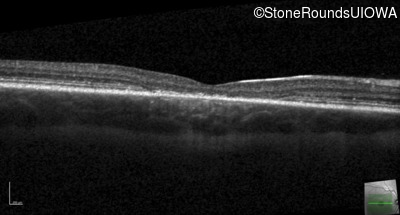

Age at visit: 14 years

Age at visit: 15 years